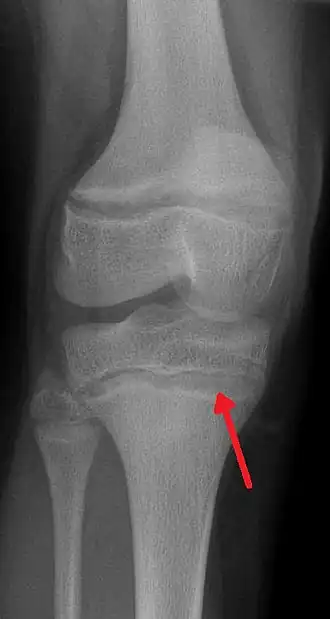

Semnele de început mai caracteristice sunt: „lizereul de plumb", care apare ca o dungă albastră-cenușie pe marginea gingiei, în dreptul dinților din față; colorația palid-cenușie a pielii; ușoare tremurături ale mâinilor.[5]